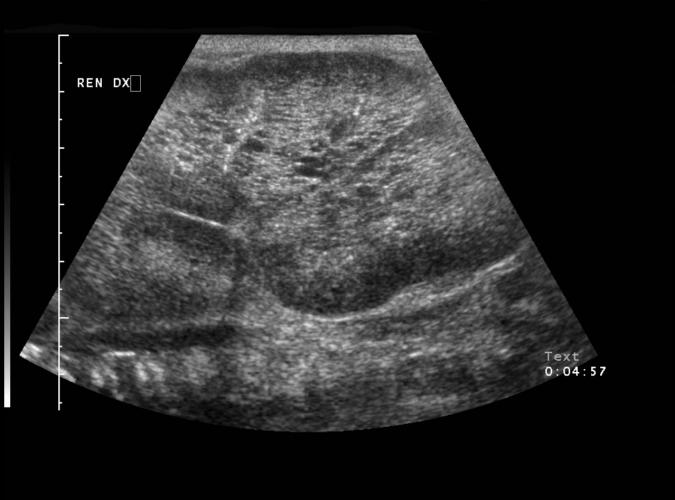

av Catherine Olsson, sonograf

Long. Höger njure

Nyfödd med bilateral polycystiska njure,10cm lång.

...se bild 9f.